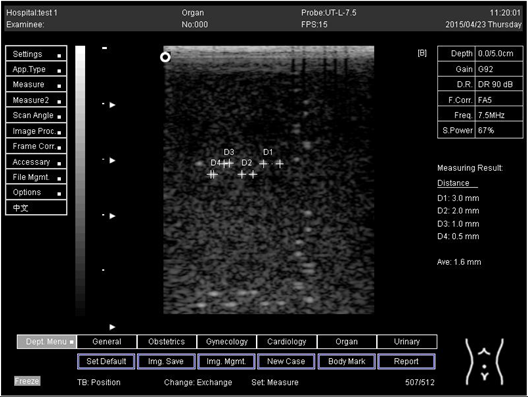

Table 6. The distance for axial and lateral resolution in mm for depth of 5.0, 6.0, 7.0 and 9.0 cm; depth for flat probe on phantom 2.

Depth (cm)DiagramDistance (mm)

5.0Axial resolution

Biomimetics 07 00130 i011

D1 = 3.0

D2 = 2.0

D3 = 1.0

D4 = 0.5

5.0 Lateral resolution

Biomimetics 07 00130 i012

Regarding phantom 2, only linear probes were applied. This is because phantom 2 is shorter than phantom 1, and the linear probe had a lower penetration setting compared to the curve probe. Therefore, a linear probe is more suitable for the phantom. Based on the results recorded on phantom 2, axial and lateral resolution measurements were still under an acceptable value since the percentage difference between the actual distances was less than 2% (Table 6).